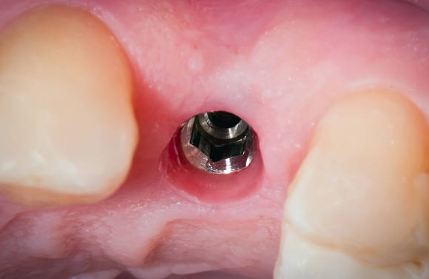

3. 2차 시술

인공치근이 잇몸뼈에 잘 자리 잡은 후, 덮어진 잇몸을 다시 열어 인공치근을 밖으로 노출시킵니다. 이때 진행하는 시술을 인공치근과 지대주를 연결하는 2차 시술이라 합니다. 지대주는 인공치근과 치아머리 크라운을 연결하는 기둥 역할을 하며, 2차 시술 후 잇몸이 완치되는데 약 1~2주 정도 걸립니다.